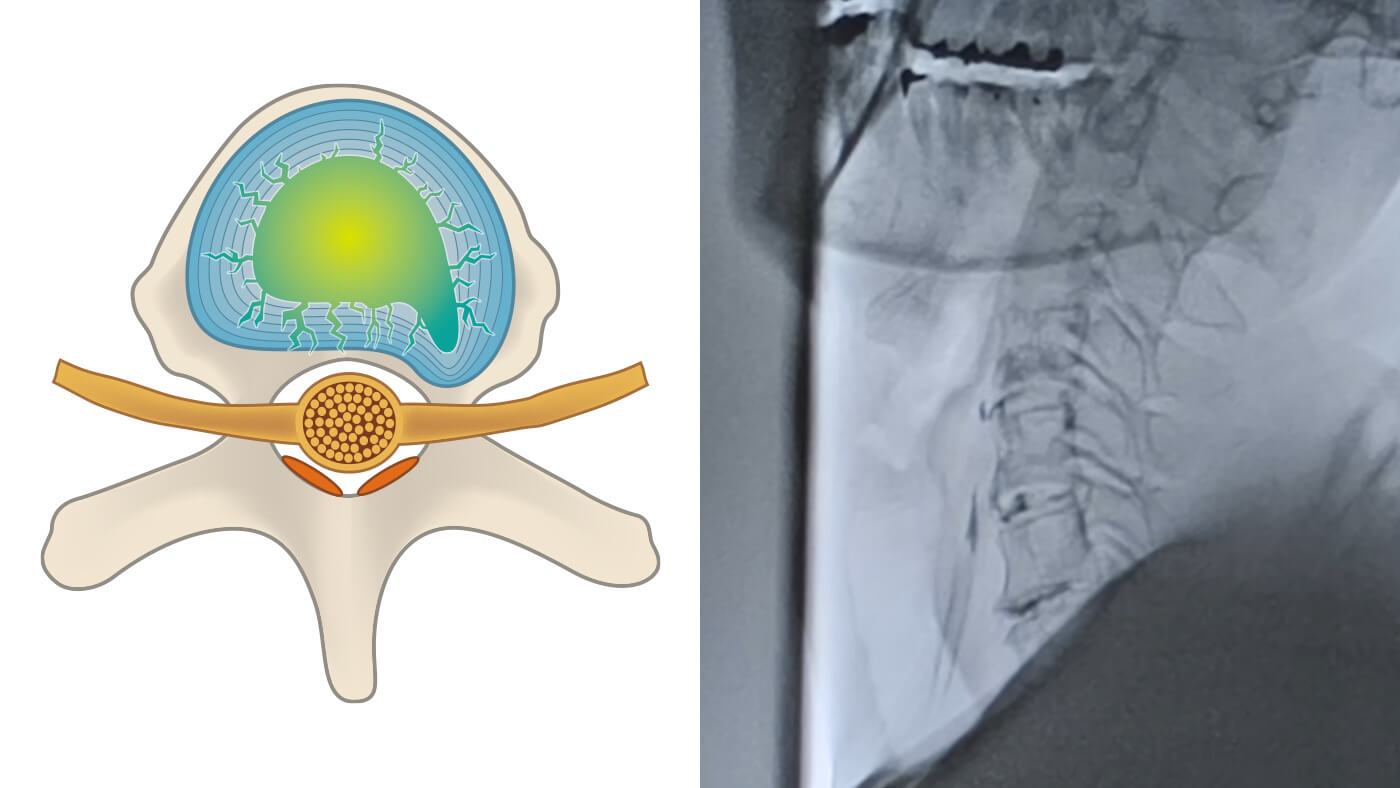

2. 椎間板の「漏れ」を検査で確認

椎間板造影検査(アニュログラム)で椎間板の状態や漏れの部位を特定します。

1. 損傷部位の特定の図解

損傷部位の特定

椎間板造影検査(アニュログラム)により、痛みの原因となっている椎間板の亀裂や損傷箇所を精密に特定します。